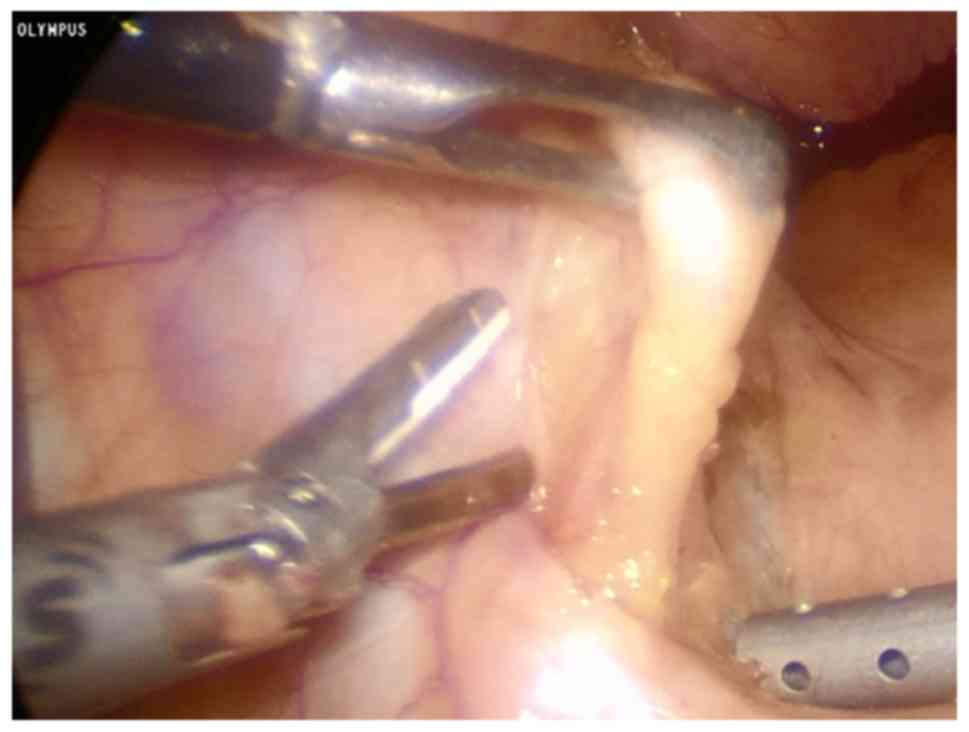

Etiologic Classification Evaluation And Management Of